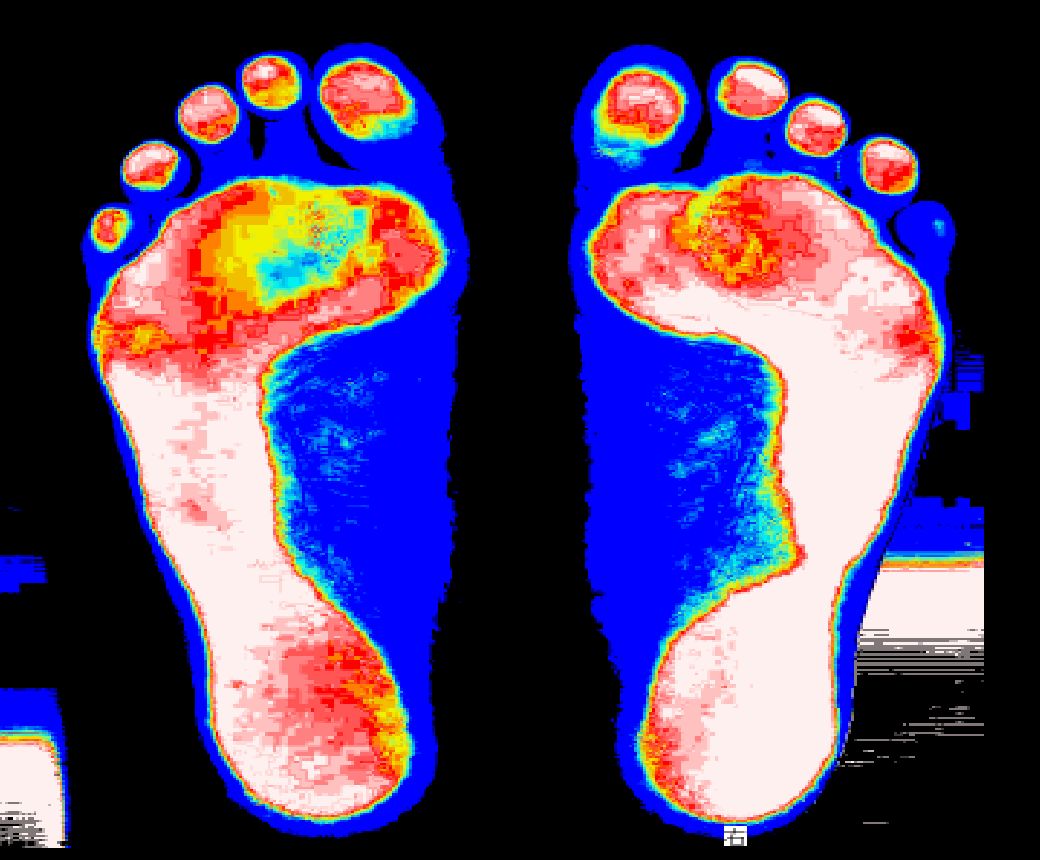

Before

身体に問題を抱えてる人は足の一部分でしか支えていません。

After

コロコロさんを転がす事で足全体で支える事ができます。

(足底圧画像)